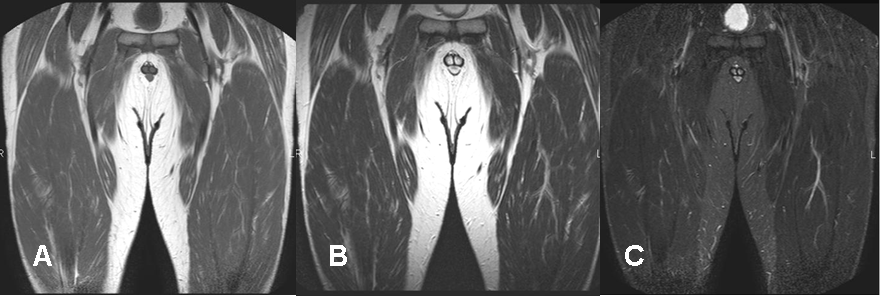

Fig 9. Señal normal del músculo.

A: RM coronal en T1. Músculo algo hiperintenso en relación al agua e hipointenso, con la grasa.

B: RM coronal en T2. Músculo hipointenso en relación con el agua y la grasa.

C: RM coronal en STIR. Músculo hipointenso en relación al agua y la grasa.